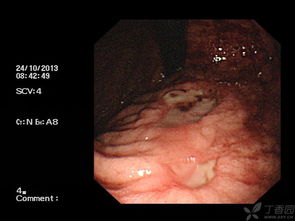

內(nèi)鏡下止血:消化性潰瘍并發(fā)出血時(shí)應(yīng)首選急診內(nèi)鏡下止血治療,若患者有劇烈嘔血不止,血壓下降,甚至出現(xiàn)出血性休克時(shí),應(yīng)密切觀察,積極補(bǔ)液、輸血,待休克糾正后再行內(nèi)鏡診治。